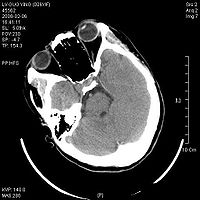

脑干损伤CT图

8.CT扫描 是目前辅助诊断颅脑损伤的重要依据。能显示颅骨骨折、脑挫裂伤、颅内血肿、蛛网膜下腔出血、脑室出血、气颅、脑水肿或脑肿胀、脑池和脑室受压移位变形、中线结构移位等。病情变化时应行CT复查。

9.MRI 急性颅脑损伤患者通常不作MRI检查。但对病情稳定的弥漫性轴索损伤、大脑半球底部、脑干、局灶性挫裂伤灶和小出血灶、等密度亚急性颅内血肿等,MRI常优于CT扫描。

2.颅脑CT、MRI扫描 原发性脑干损伤表现为脑干肿大,有点片状密度增高区,脚间池桥池四叠体池及第四脑室受压或闭塞。继发性脑疝的脑干损伤除显示继发性病变的征象外,还可见脑干受压扭曲向对侧移位,MRI可显示脑干内小出血灶与挫裂伤,由于不受骨性伪影影响,显示较CT清楚。